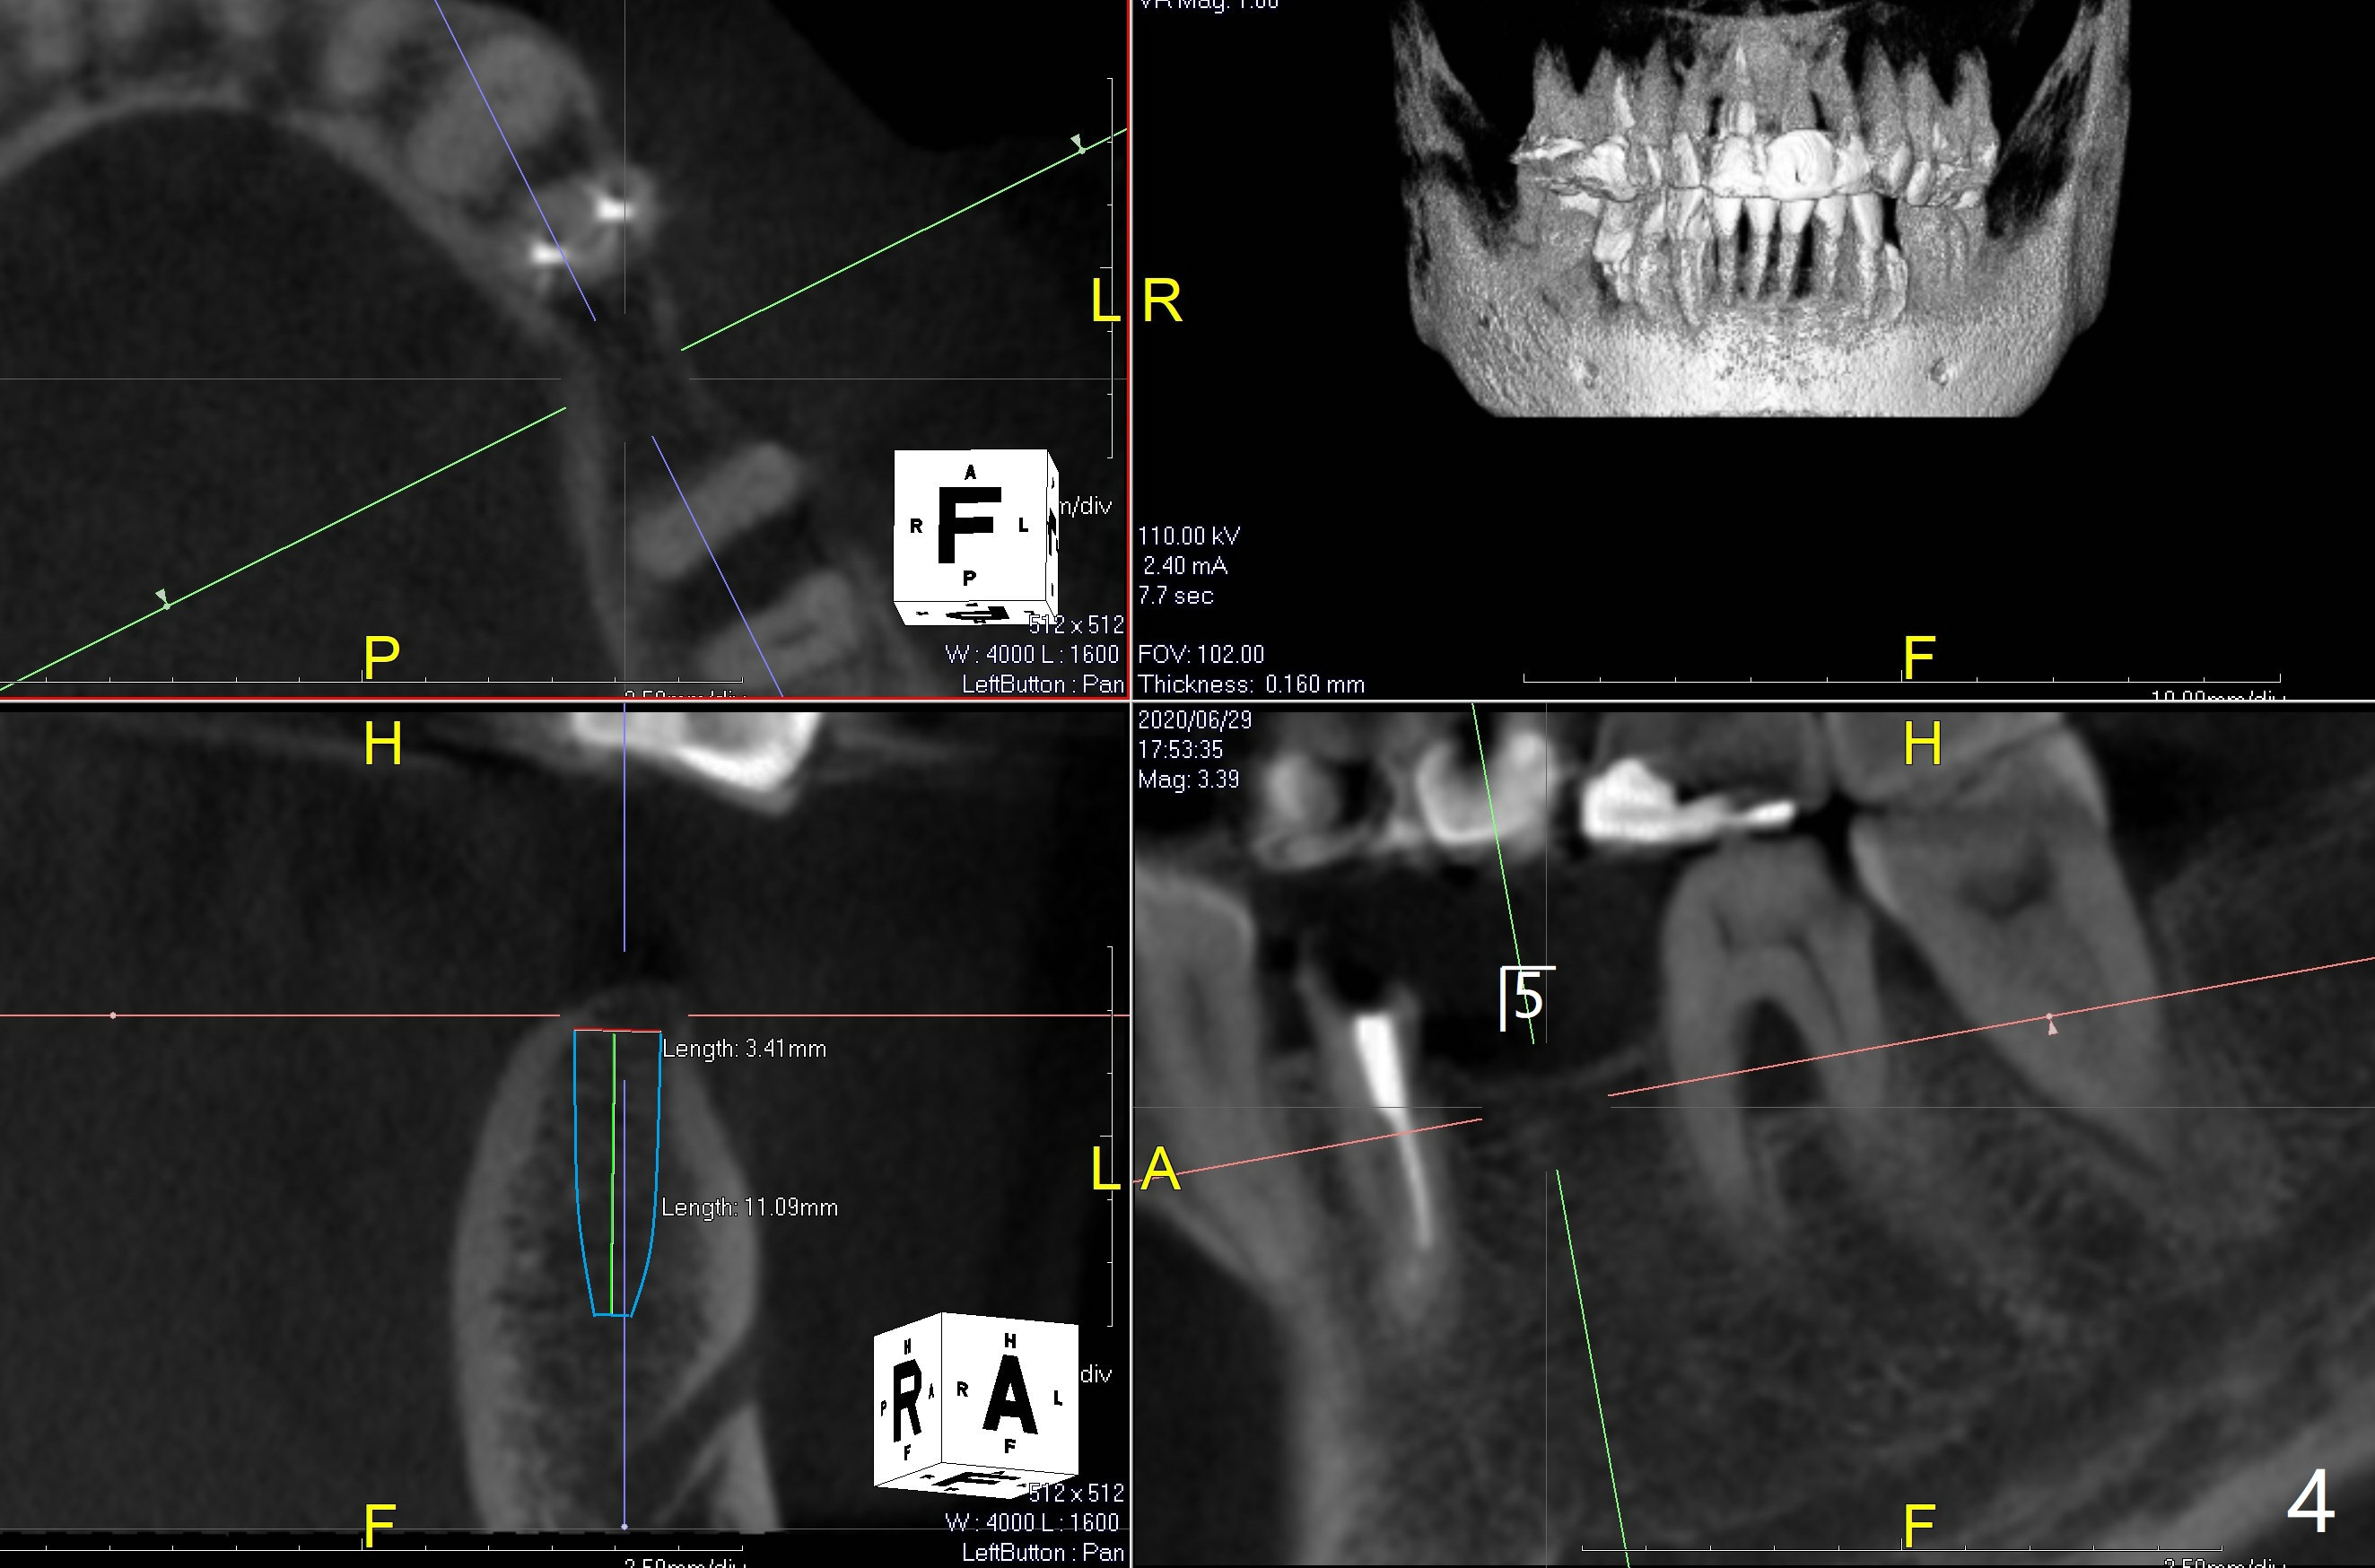

63岁女对肾上腺素和90%以上抗生素过敏,左上5(短根,巨大根尖阴影,图一),左下6(根分叉感染,远中龋齿(图二:*),左下4(牙齿断裂略微龈下:图二,五)似乎很难保留,左下5骨质宽度,高度也允许植牙(图四)。由于左上5需要提升术,可能出现上颌窦感染,Z Pack是否引起过敏反应不确定,拔牙植骨与提升植牙分期做(术前拍摄根尖片)。而下颌一期完成。